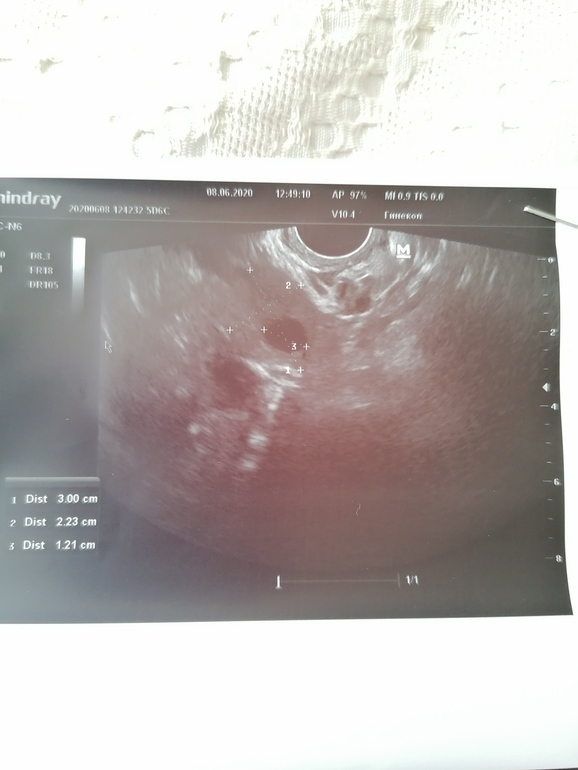

Напишу как у меня. Этот цикл очень странно начался. На 4 ДЦ на узи нашли 2 ДФ один 13, второй 12.2 в разных яичника. В левом кстати есть ЖТ с прошлого цикла угасающе. И теперь мне интересно когда же может быть овуляция с такими фолика и на 4 ДЦ??? У меня впервые так рано будет овуля. Обычно цикл 29 дней и овуля на 16 ДЦ.

Домин.фолл должен иметь ооочень четкие и ровные края, прям как шарик. Размытые края и неровный шар - это жт или фолл.кисты, там уже по эхогенности надо смотреть и кровотоку

Для 4дц слишком большие фолликулы. Второй больше похож на ЖТ. Я бы помониторила весь цикл.

Да я сама в шоке. Второго фолика и нет на фото, это ЖТ с прошлого цикла 8мм. Второй фолик как и первый круглый